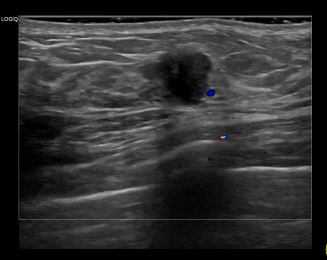

상기환자는 좌측유방 만져지는 멍우리로  내원하신 40대 초반 여성분으로 의심스러운 좌측 혹 조직검사 시행해 유방암 진단되었습니다.